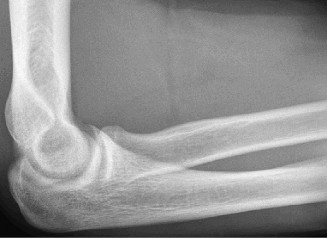

Standard radiographic evaluation of the thrower's elbow must include true anteroposterior (AP), lateral, oblique, and axial (cubital tunnel) views. In this patient, the AP view may appear relatively unremarkable, though subtle hypertrophy of the medial epicondyle or radiocapitellar sclerosis may be noted. The true lateral radiograph is highly informative, often demonstrating the presence of a posterior olecranon osteophyte.

However, the most critical view for diagnosing VEO is the internal rotation oblique view, or a specialized axial view of the olecranon fossa. In our patient's radiographs, we observe a distinct, hypertrophic osteophyte on the posteromedial aspect of the olecranon process. There are also faint radiopacities within the posterior compartment, highly suggestive of intra-articular loose bodies resulting from the fragmentation of these osteophytes.